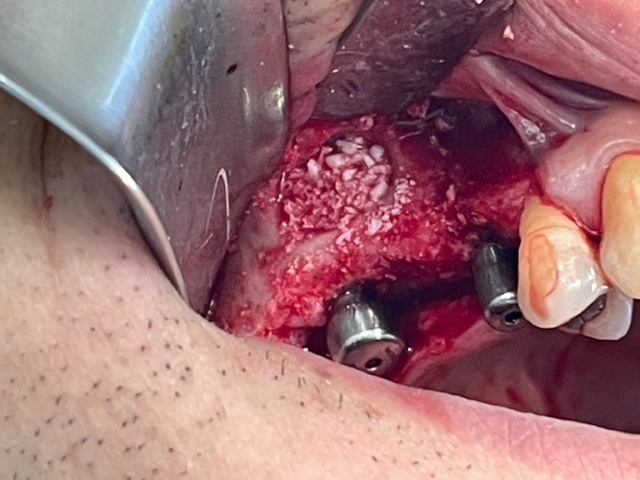

→ Pose du ou des implants

Durant cette étape, le praticien pose les implants dentaires pour remplacer les racines manquantes. À l’issue de cette intervention, vous sentirez des implants couverts par la gencive, et qu’ils sont mis en “nourrice” : cela permet à l’os de cicatriser autour des implants.

L’implant dentaire est placé dans la mâchoire sous anesthésie locale dans la majorité des cas, parfois sous anesthésie générale.